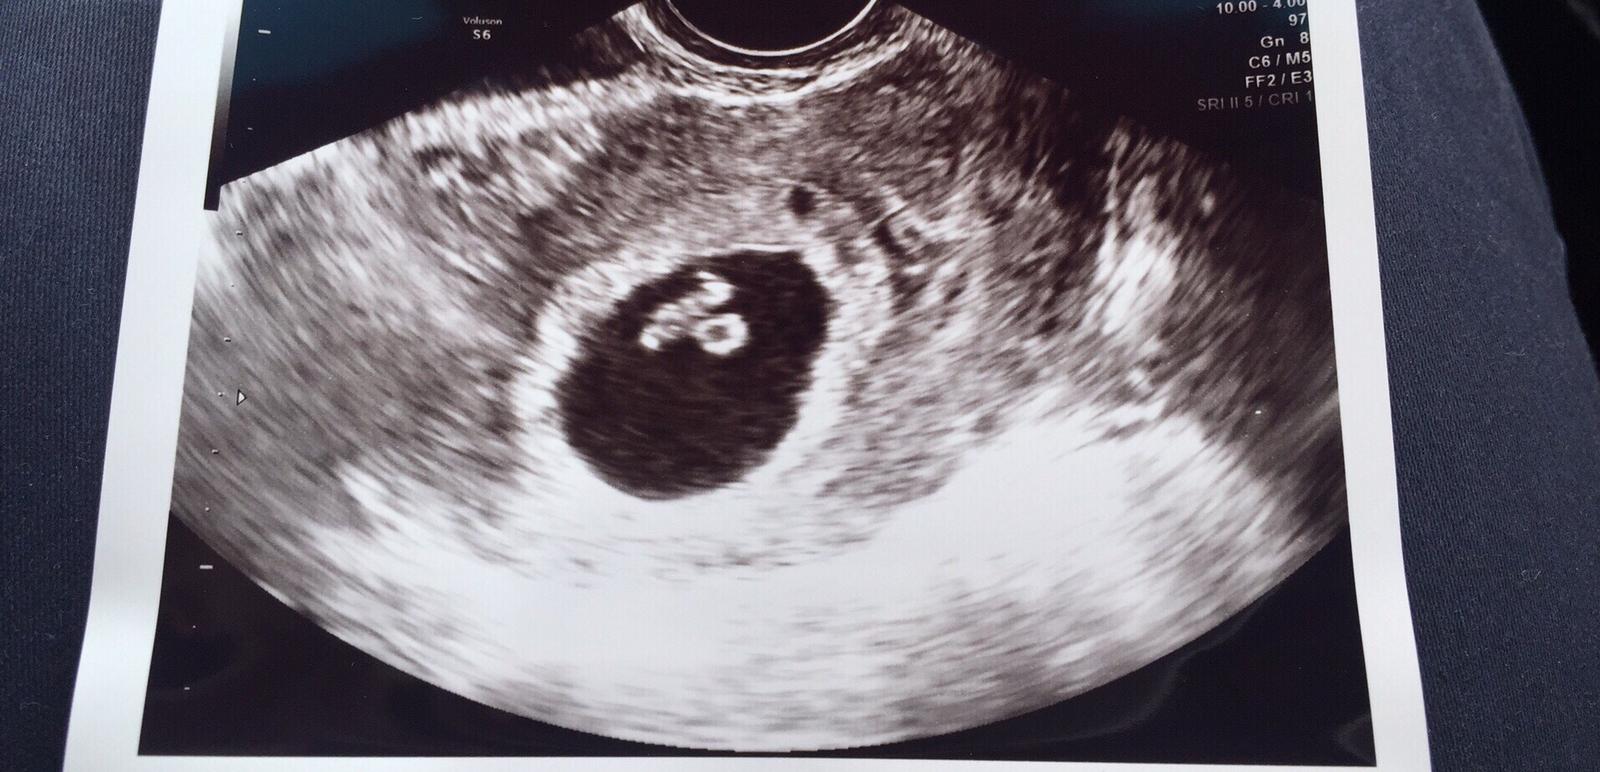

@matik7 velmi Ti drzim palceky na zajtrajsie jasne potvrdenie tehulkovania...Daj nam potom vediet a myslim, ze uz aj ❤ budes vidiet 😉